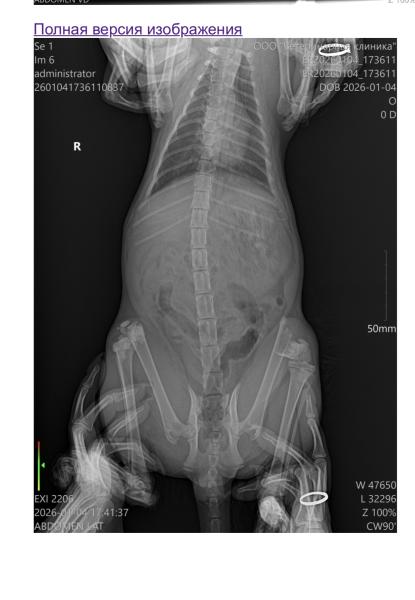

Недавно подобрала маленькое, пушистое чудо, на вид ему буквально 4-6 месяцев, не так давно со мной, но уже считаю его членом семьи. По плохим стечениям обстоятельств, маленький выпал с 7-го этажа. Нужна операция: метод остеосинтеза интрамедуллярный ( вставлять спицы); диагноз: перелом блоков бедренных костей